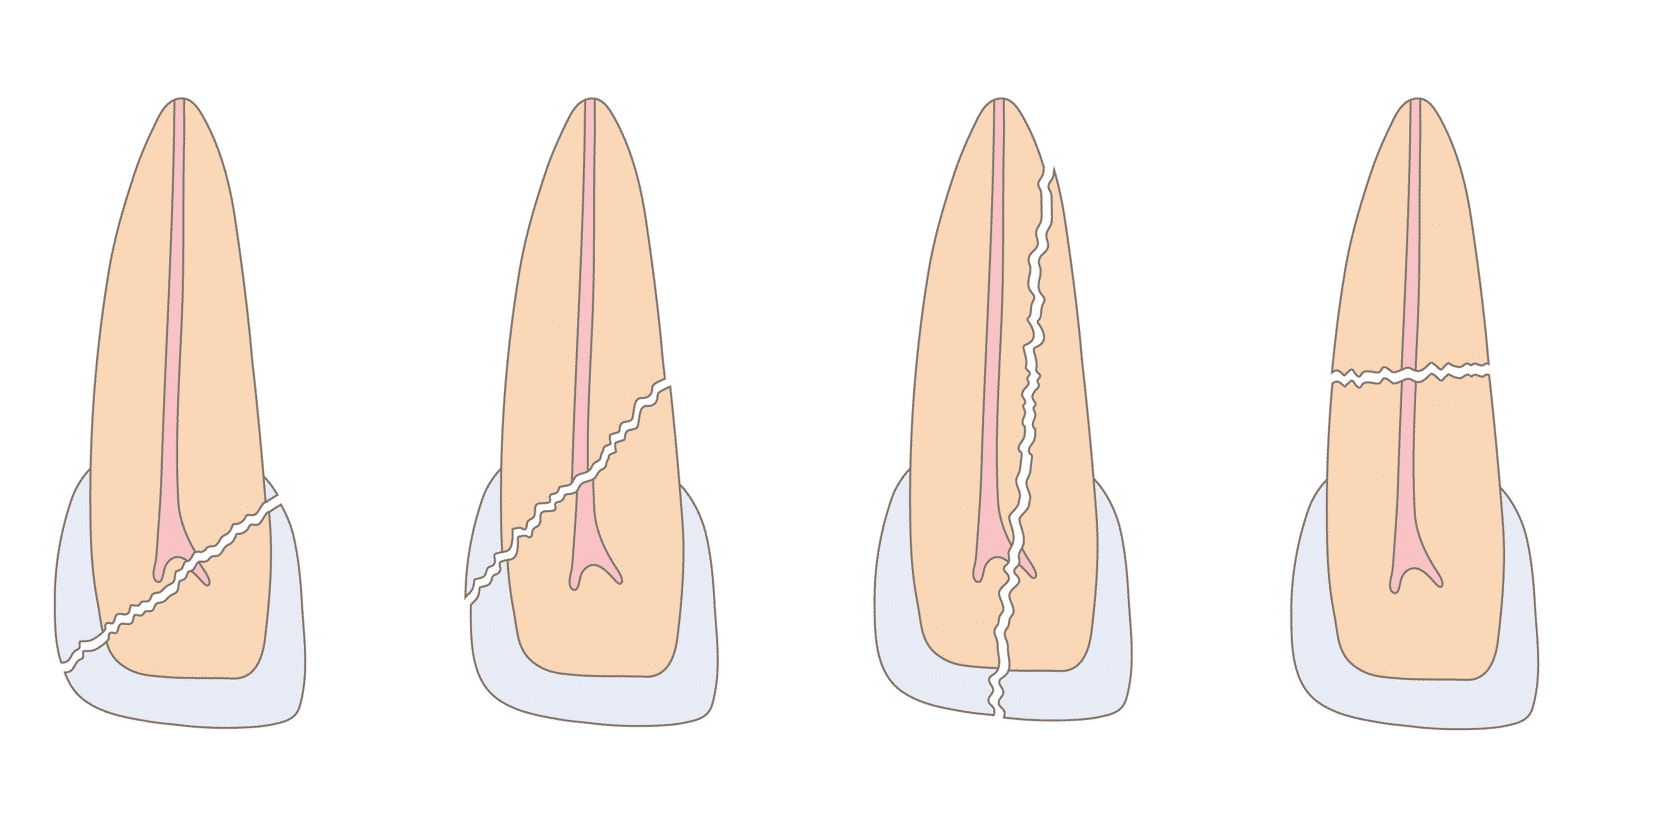

In de tweede module behandelen we de belangrijkste mondziekten, cariës, tandvleesontstekingen, tanderosie en tandletsels.